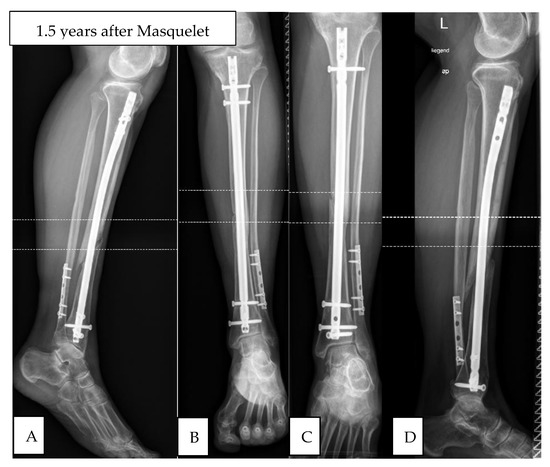

Clinical Observations of the Effectiveness of the Masquelet Induced Membrane Technique in the Treatment of Critical Long-Bone Defects of the Lower and Upper Extremities

by Kamil Kołodziejczyk, Aleksander Ropielewski, Rafał Garlewicz, Marcin Złotorowicz and Jarosław Czubak

Medicina 2024, 60(12), 1933; https://doi.org/10.3390/medicina60121933 - 24 Nov 2024

Background and Objectives: Successful treatment of severe trauma and fractures of the long bones with successful healing and bone union is still a significant challenge for surgeons. Unfortunately, up to 10% of long-bone fractures develop bone healing disorders. The aim of this study was to evaluate the results of treating bone defects with different etiologies in the upper and lower extremities using the induced membrane technique. Materials and Methods: We prospectively evaluated the radiological and clinical outcomes of 45 patients with severe bone defects treated with the induced membrane technique during the period from May 2021 to October 2023. The time to bone defect regeneration, size of the bone defect, and the cost of treatment were evaluated. Functional outcomes were assessed using the Disabilities of the Arm Shoulder and Hand (DASH) scale, SF-36, and the Lower Limb Functional Index (LLFI). Results: The mean follow-up time was 31 months (12–35). There were 20 patients with upper extremity bone defects and 25 with lower extremity bone defects. The mean defect length was 7.9 cm for the upper extremity (3.5–18) and 5.3 cm for the lower extremity (3–11). The mean times to achieve bone union and remodeling were 6.0 months (3–12) and 9 months (3–13) for the upper and lower limbs, respectively. Clinical evaluation at the end of treatment (achieving bone union) showed statistically significant improvements in the DASH, SF-36, and LLFI scales for pre- and postoperative outcomes. There was no statistical significance in the SF-36 clinical scale scores after surgical treatment compared to reconstructive treatment of upper and lower extremity bone defects. Results: The presented reconstructive approach to the treatment of bone defects and healing disorders and extensive analysis demonstrate the effectiveness of the induced membrane technique in a short follow-up period, with a relatively high level of patient comfort and good clinical results in the treatment of severe bone defects with particularly infectious etiologies. Full article